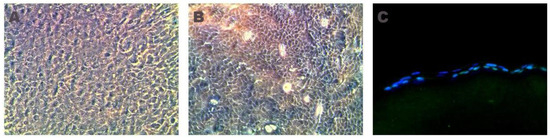

2.1. Cell Culture

4.2. Cell Culture